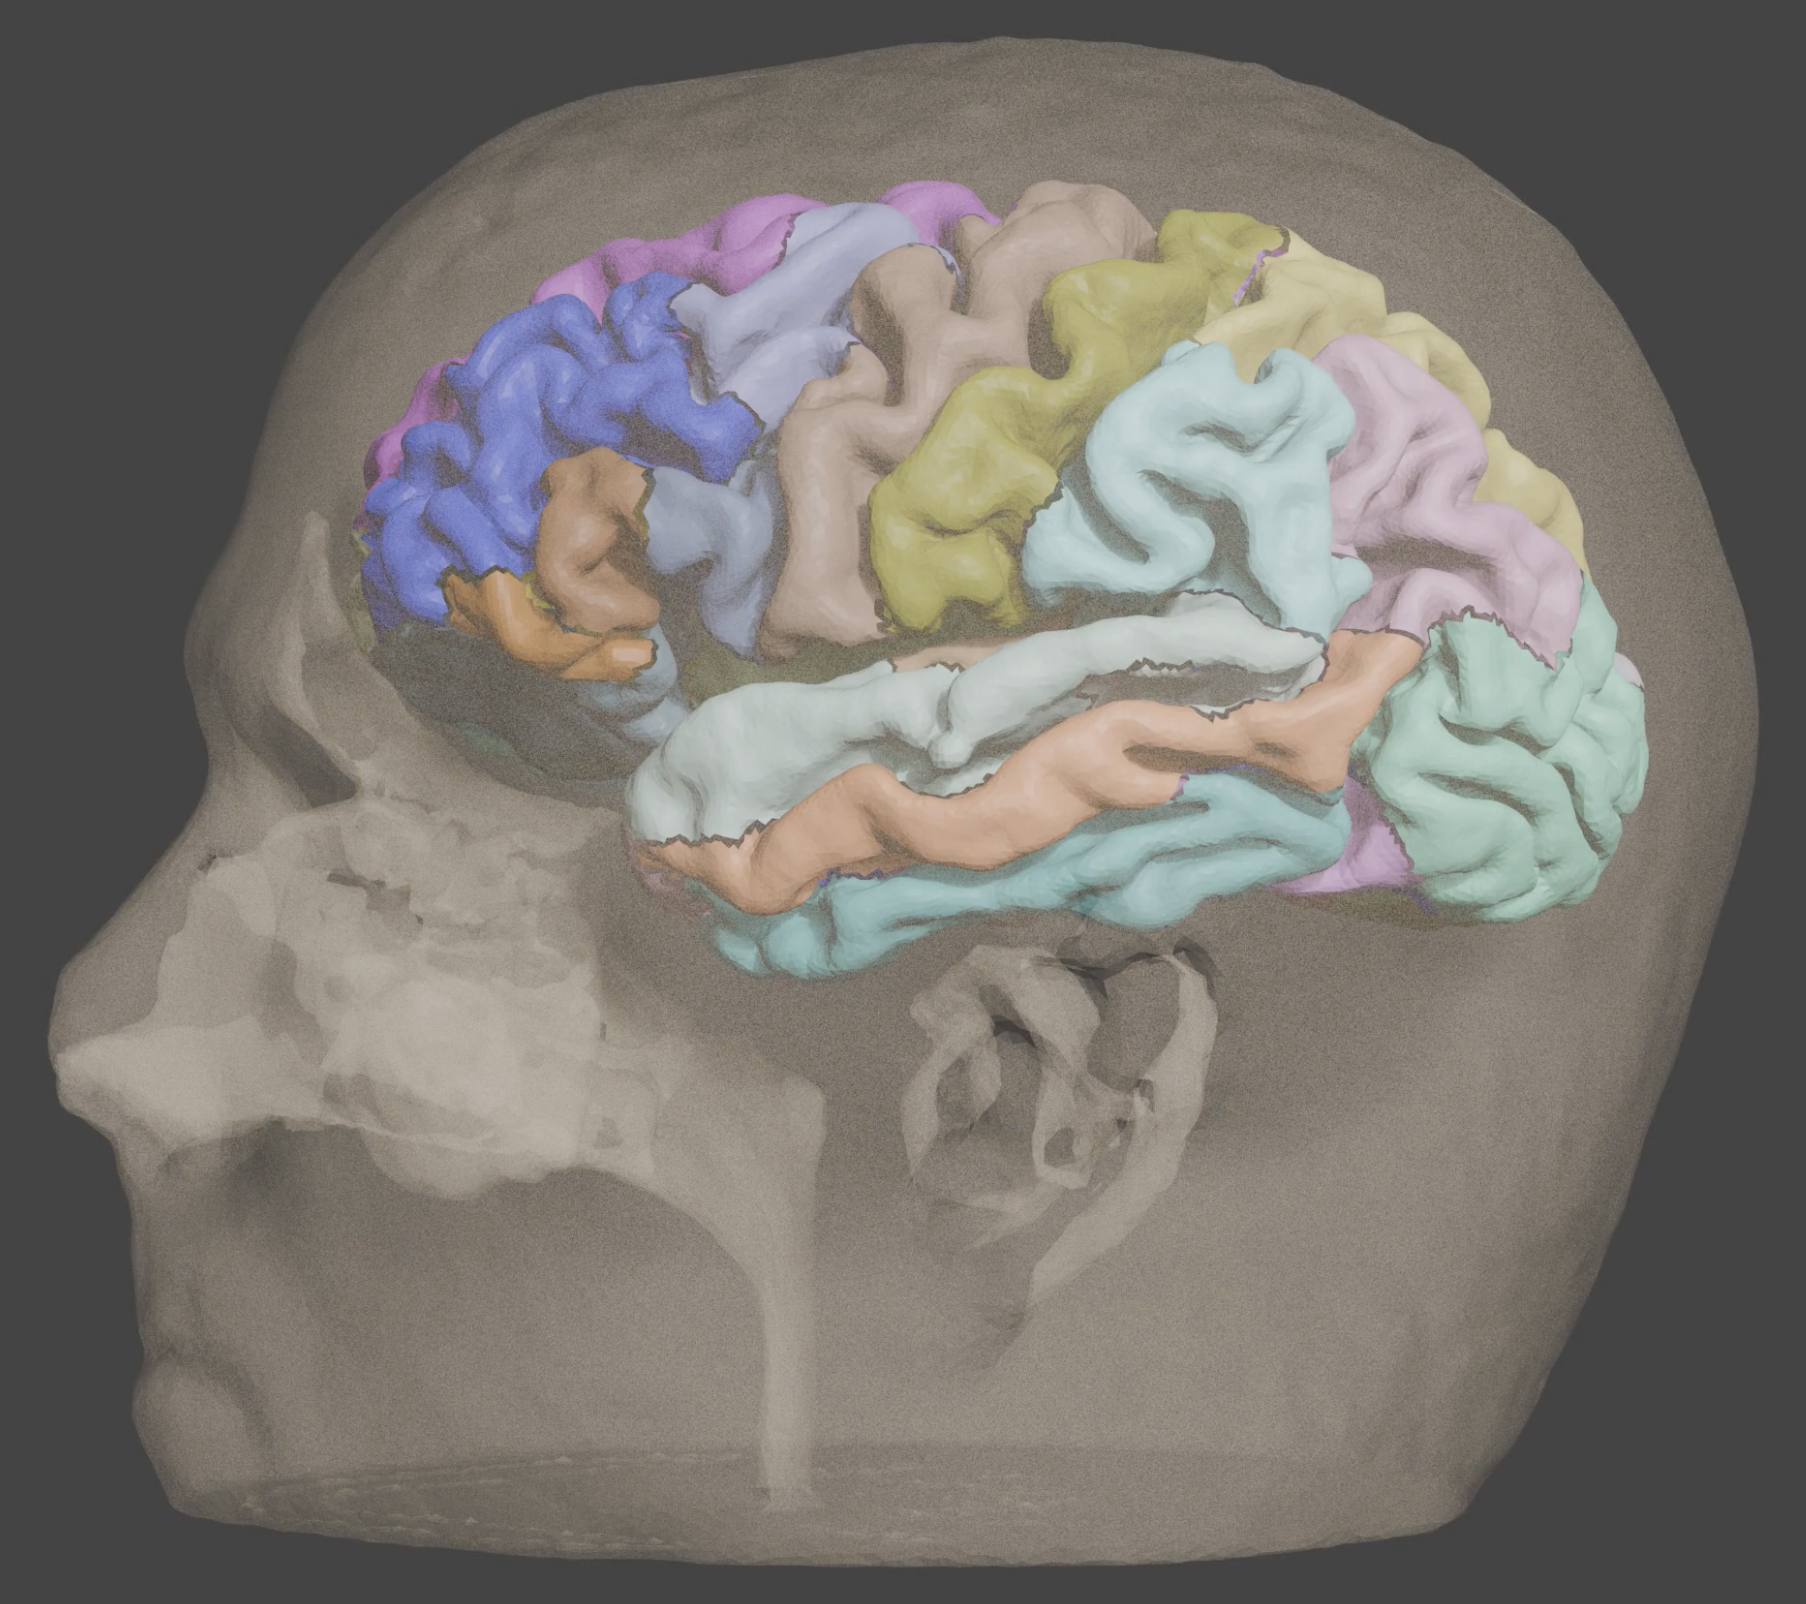

Multiple cortical atlases are automatically aligned to subject space, here showing DKT.